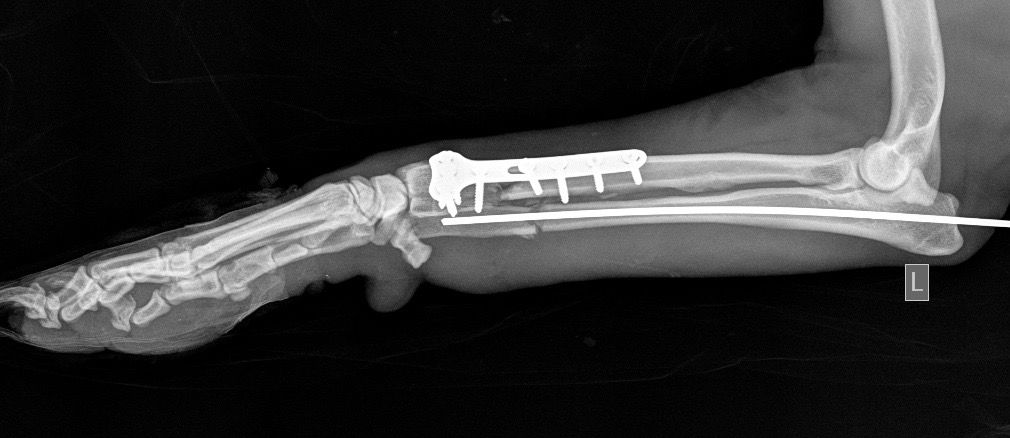

Η κα Μακρή δημοσίευσε σήμερα στο facebook την γνωμάτευση του κτηνιάτρου σχετικά με την εξέλιξη της υγείας του ζώου. Σε αυτή αναφέρεται ότι: «Ο σκύλος έφερε συντριπτικά ενδοαρθρικά κατάγματα με μετατόπιση στο κάτω τρίτο του αριστερού αντιβραχίου και στο κάτω τρίτο του αριστερού μηριαίου. Ολοκληρώθηκε με επιτυχία η πρώτη χειρουργική επέμβαση που αφορούσε την ανάταξη και οστεοσύνθεση του αριστερού αντιβραχίου. Λόγω της σοβαρότητας του κατάγματος η διάρκεια της χειρουργικής επέμβασης ήταν 4 ώρες και 25 λεπτά και ο σκύλος ανένηψε φυσιολογικά».